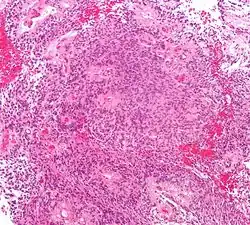

Micrograph of an ependymoma. H&E stain. | |

Ependymomas are composed of cells with regular, round to oval nuclei. There is a variably dense fibrillary background. Tumor cells may form gland-like round or elongated structures that resemble the embryologic ependymal canal, with long, delicate processes extending into the lumen; more frequently present are perivascular pseudorosettes in which tumor cells are arranged around vessels with an intervening zone consisting of thin ependymal processes directed toward the wall of the vessel.[5]

The World Health Organization classifies ependymomas as Grade I-III. Grade I tumors are low-grade and include the subependymoma subtype, which is more common in adults. Grade II tumors include myxopapillary and conventional ependymoma, which are identified by the presence of perivascular pseudorosettes. Grade III anaplastic ependymomas are the most severe and fast-growing tumors.[4]